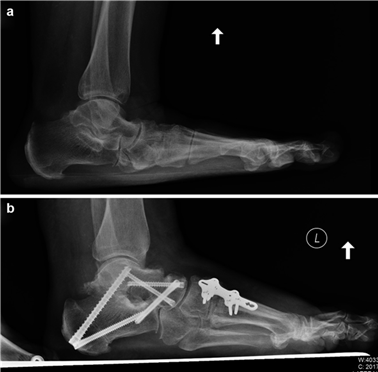

To achieve multiplanar correction, the surgeon must address the sagittal, coronal, and transverse planes. The first metatarsal is plantarflexed to restore the longitudinal arch, rotated out of pronation to realign the sesamoids, and translated laterally to close the IMA. Subchondral drilling or feathering is performed to optimize the biological environment for fusion. Fixation is traditionally achieved with two or three crossed solid or cannulated screws (typically 3.5mm or 4.0mm). Recently, plantar or medial locking plates have gained immense popularity due to their superior biomechanical construct, allowing for earlier weight-bearing. Bone graft or orthobiologics may be packed into the arthrodesis site to stimulate osteogenesis.

Positioning of the fusion is the most critical step of the operation. The hallux must be positioned in 10-15 degrees of valgus, 15-20 degrees of dorsiflexion relative to the first metatarsal, and neutral rotation. Excessive dorsiflexion causes shoe impingement, while insufficient dorsiflexion leads to vaulting during gait and interphalangeal joint arthritis. Fixation is most reliably achieved using a pre-contoured dorsal locking plate combined with a lag screw crossing the fusion interface.

| Transfer Metatarsalgia | 5 - 15% | Excessive shortening or dorsal elevation of the first metatarsal (malunion). | Orthotic management (metatarsal pads); Weil osteotomies of lesser metatarsals; Plantarflexing 1st TMT revision. |

Clinical & Radiographic Imaging Archive